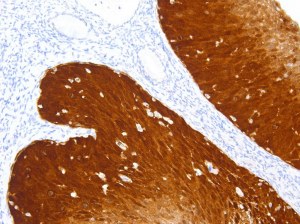

O Kit LymphoSign desempenha um papel crucial no estabelecimento de diagnósticos precisos e planos de tratamento para o linfoma não Hodgkin. Aproveitando os níveis de expressão de RNA de mais de 130 marcadores genéticos relevantes, este método de última geração fornece informações valiosas sobre a progressão da doença. O seu protocolo simples e rápido e a adequação para amostras desafiadoras tornam-no uma ferramenta poderosa na investigação do linfoma não Hodgkin e no tratamento de pacientes.